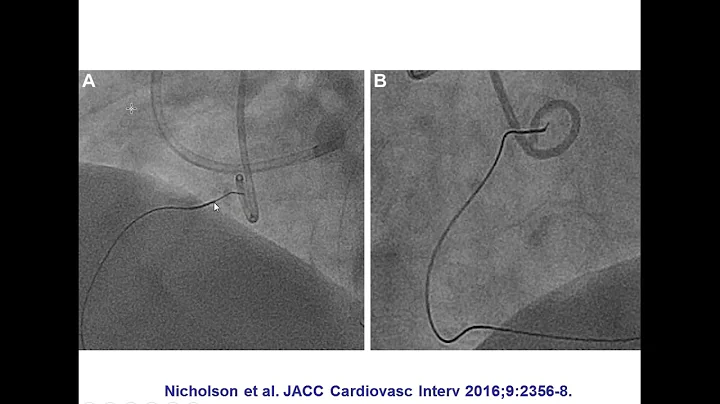

A patient was referred for PCI of a RCA CTO due to medically refractory angina. The RCA CTO had an ambiguous proximal cap, ...